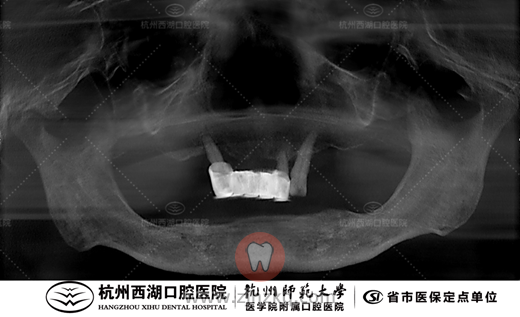

术后即刻戴牙CBCT照片如下